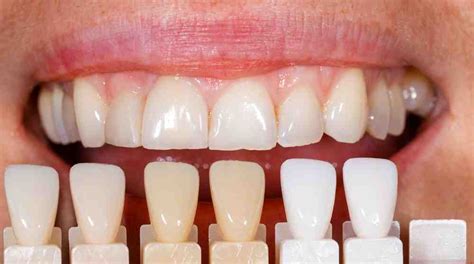

Las carillas de porcelana son finas láminas de cerámica que se fabrican a medida para cada paciente. Se diseñan para cubrir la parte frontal de los dientes, mejorando su forma, tamaño y color, ofreciendo una solución duradera y estéticamente agradable. Las carillas ofrecen una apariencia natural y pueden durar más de una década con el cuidado adecuado. Son resistentes a las manchas y replican el aspecto de los dientes naturales. En términos generales, todos los tratamientos con carillas son rápidos, poco invasivos y prácticamente indoloros.

Las carillas pueden ser de composite o de porcelana, en este caso las carillas de porcelana poseen una capacidad natural para reflejar la luz y adaptarse a la tonalidad de los dientes. El precio de los tratamientos con estas carillas suele ser mayor debido a la utilización de materiales de alta calidad, los cuales tienen un impacto significativo en la calidad y durabilidad de los resultados obtenidos.